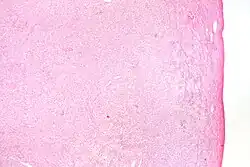

| Micrograph of a granulosa cell tumour, a type of sex-cord–gonadal stromal tumour. H&E stain. | |

Definitive diagnosis of these tumours is based on the histology of tissue obtained in a biopsy or surgical resection. In a retrospective study of 72 cases in children and adolescents, the histology was important to prognosis.[8]